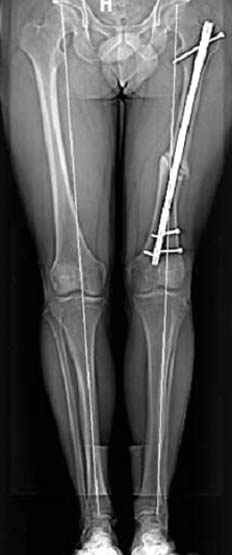

но в целом не вижу ничего ненормального в выполнении фигурных остеотомий - одномоментная коррекция оси, полная мобильность суставов, да и разрезы 4-8 см - что тоже не преступление перед человечеством. Может быть, я бы стал сторонником поперечных остеотомий ипостепенной коррекции в аппаратах, ежели бы прошел через курганскую школу, но в силу обстоятельств столкнулся с другим подходом к коррекции деформаций, который вполне эффективен и надежен, у меня не сложилось разочарования в этой технике. Поэтому и представленный раннее случай деформации бедра я бы решил сегментарной остеотомией бедра и фиксацией запирающим гвоздем - своего рода эндопротезом проксимального бедра и для больной, мне кажется, более комфортно иметь фиксацию штифтом

нежели в громоздком аппарате, постоянный уход за спицами и вращение гаек.

На рисунке N1 предоперационный план лечения ложного сустава шейки бедра- линия ложного сустава, угол и направление введения импланта, клиновидная остеотомия в градусах и миллиметрах, второй снимок после коррекции, расчет, на сколько удлиняется конечность и размеры импланта;

N3 рисунок окончательный снимок, после операции моя рентгенограмма должен выглядеть примерно как эта картина. На N4 снимке клин перед удалением; N5 послеоперации 3 нед.; N6 окончательная рентгенограмма.

пластическая модель; и коррекция бедра аппаратом Илизарова.

Узкий к-м канал - тонкий гвоздь- усталостный перелом дистальных винтов - развитие нестабильности и как ее результат остеолиз вокруг гвоздя - деформация анатомической оси бедра. Похоже, что я понял почему аппарат, а не новый гвоздь:-)